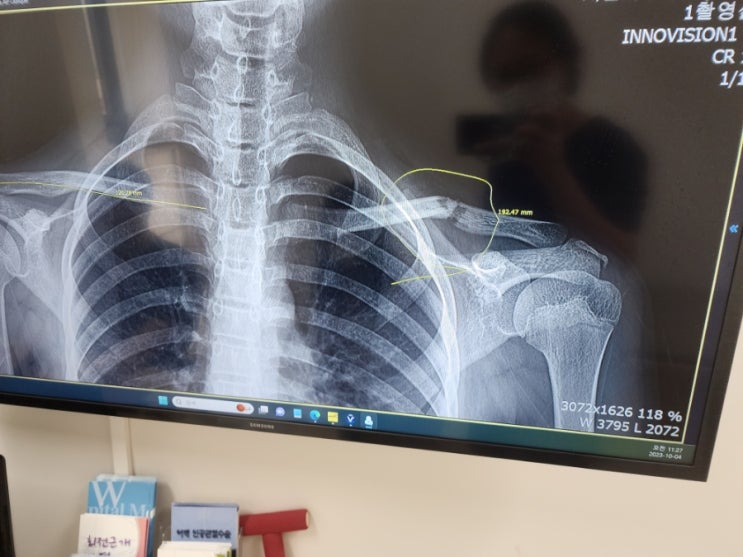

아이 쇄골 골절 후기 10개월만에 끝

아이랑 저녁에 운동장에서 놀다가 넘어졌는데 쇄골이 부러졌다... 그 당시에 넘어지는데 진짜 뭐랄까 그냥 ...